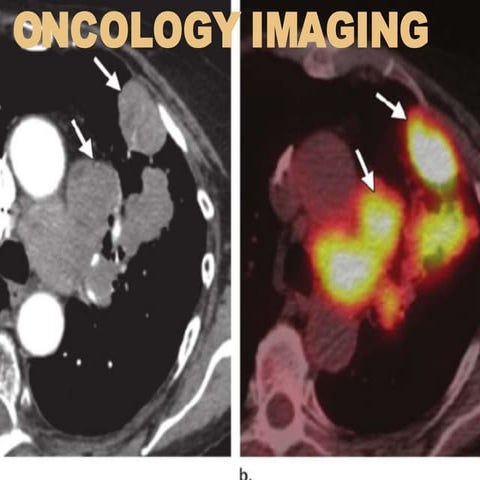

Oncology

Primary presentation: diagnosis: unknown primary

malignancy,differentiationofbenignandmalignantlesions

of e.g. a solitary lung nodule, Fig.5, especially in case of

discrepant clinical and radiological estimates of the

likelihood of cancer;